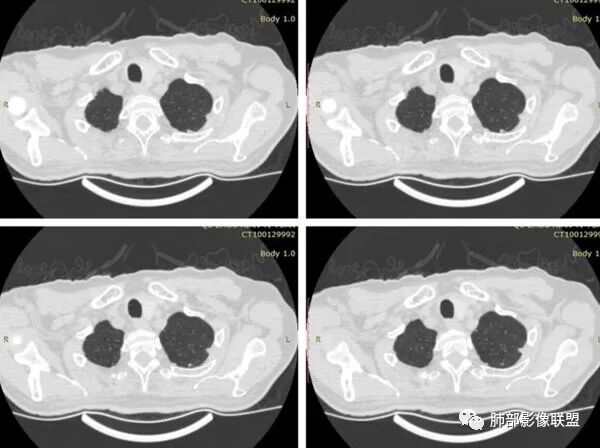

有栽赃吗?

这种属于宽基底与胸膜相连,附近胸膜增厚

栽赃是局部外侵犯

这里没有栽赃

如下图病例红色箭头的是典型栽赃:

南边 :

而该病例栽赃不明显,与增厚的胸膜分界比较清晰

下面这个病例这也是栽赃